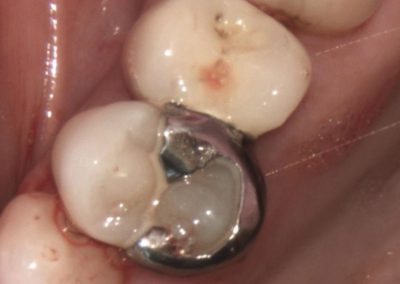

Healthy Smiles These are more advanced examples of different treatments available.All cases shown were carried out by Dr R Khurana unless otherwise stated. Immediate implants Anterior Mandible Bone Regeneration Anterior Mandibular Implant Bridge Maxillary Anterior Implant Bridge Implant stabilised ‘Life Like’ replacement dentures Implant Bridge after 10-years with zero bone loss Implant examples including ZBLC concepts Adhesive Bridge solution for a missing premolar Multidisciplinary care Orthodontics, Replacement veneers and composite bonding Adhesive Bridge solution for missing central incisors Replacement crown, Veneer and Composite Bonding Replacement Crowns and Veneer Injection Moulding using Composite Resin Equilibration Tooth Whitening to treat Developmental Discolouration